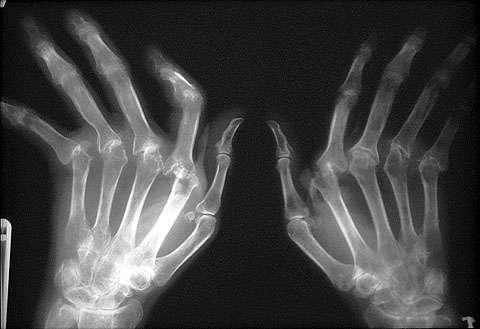

-work started on ibuprofen in 1950, as a treatment for rheumatoid arthritis

rheumatoid arthritis is an inflammation in joints in one's body